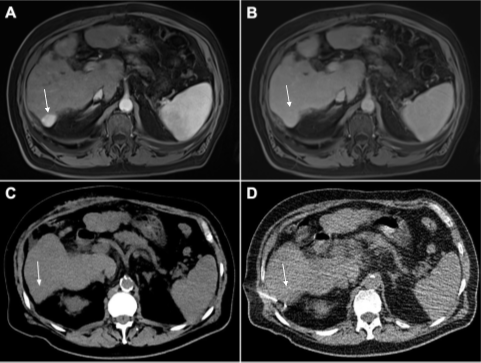

In line with this plan, a scheduled MRI three months later showed slight progression of a subcapsular tumor in segment VII, which grew to 24 x 19 mm in size (Figure 1 A B). In addition, a rise of AFP to 97 ng/mL was seen. Thus, the tumor board recommended repetitive surgery, which concurred with the patient’s wishes.

Considering the unexpected outcome of the first surgery, proper intraoperative identification of the lesion was deemed crucial for successful resection. In a two-step approach, the interventional radiologist first marked the tumor by CT-guided implantation of radioactive seeds (Figure 1 C D)

Figure 1: Primary liver tumor in liver segment VII (arrow). (A) Hyperintensity is seen in arterial phase and (B) washout in portal phase of multiphasic MRI of the liver (both marked by arrows). Both are typical features of hepatocellular carcinoma. (C) Native CT of the slightly hypodense lesion in segment VII (arrow). (D) Percutaneous implantation of the 125I seed.

according to anatomical landmarks (arrow). Subsequently, re-laparotomy and atypical resection of the marked lesion was conducted. Iodine-125 radiation of the seed with peak values in the resected tissue could be identified using a gamma probe. Intraoperative X-ray of the specimen verified complete removal of the seed (FIGURE 2).